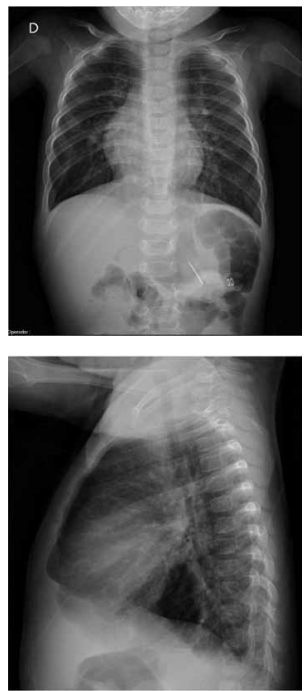

Com base na radiografia de tórax e no eletrocardiograma

de um lactente de 9 meses, apresentados a seguir, qual

é a malformação cardiovascular mais provável?

(Arquivo pessoal; imagem usada com autorização)